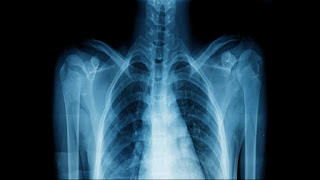

Here, data on a heterogeneous group of 9,041 postmenopausal women were collected over 6 years, with researchers specifically examining bone mineral density : an indirect indicator of osteoporosis and risk of fractures. Using home addresses for estimates of nitric oxide, nitrogen dioxide, sulfur dioxide and PM10 particulates (pollution less than 10 micrometers, the diameter of a red blood cell), researchers found that when pollution increased, bone mineral density decreased all bone areas of the body, including the neck, spine and hip. “Our findings confirm that poor air quality can be a risk factor for bone loss, regardless of socio-economic or demographic factors,” says biomedical scientist Diddier Prada of Columbia University in New York. Previous studies have shown an association between worsening air pollution and a higher risk of bone fractures, as well as increased bone loss over time.

This research adds data on postmenopausal women in particular and on different mixes of air pollution. In particular, Prada and colleagues highlighted the link between nitrogen and the spine. A 10 percent jump in this type of pollution in 3 years was associated with an average annual loss of 1.22 percent of the bone mineral density of the lumbar spine, double the amount calculated by the team from normal aging. According to the researchers, this is most likely due to bone cell death caused by mechanisms that include oxidative stress , in which toxic molecules from the environment cause harm to the body. “For the first time, we have evidence that nitrogen oxides, in particular, contribute significantly to bone damage and that the lumbar spine is one of the most susceptible sites of this damage,” says Prada. The study alone is not enough to prove a causal relationship – that air pollution is certainly leading to bone loss – but considering the amount of research that is being formed, it seems an increasingly plausible hypothesis. It is also worth mentioning that while this particular study examined postmenopausal women, the participants involved covered a wide range of ethnic groups, places, lifestyles and socio-economic contexts, making pollution levels more likely to be, In fact, the underlying cause of bone loss. Researchers want to see further efforts made to reduce air pollution – traffic is one of the leading producers of nitrogen oxides, for example – and to identify people who might be more vulnerable (including those with osteoporosis). “Improvements in exposure to air pollution, particularly nitrogen oxides, will reduce bone damage in postmenopausal women, prevent bone fractures and reduce the burden of health costs associated with osteoporosis among postmenopausal women”says epigeneticist Andrea Baccarelli of Columbia University.